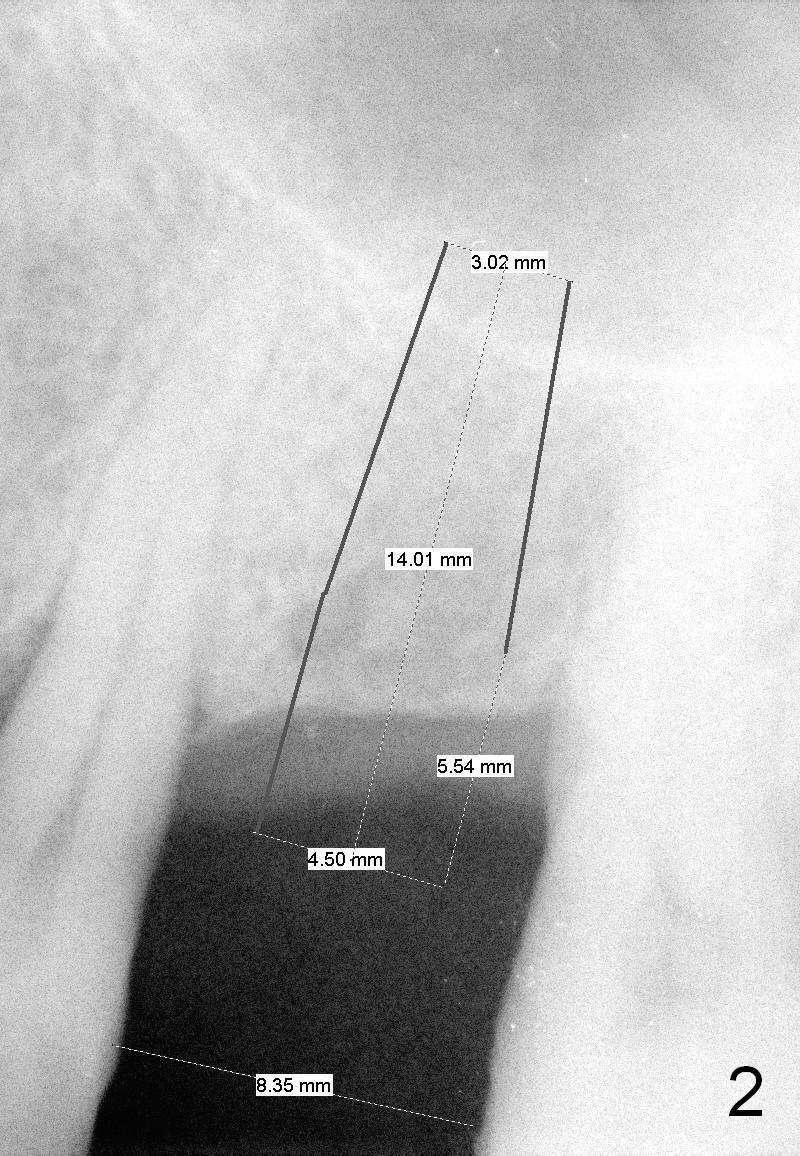

A 58-year-old man has multiple missing teeth including #14; the remaining teeth has sign of occlusal trauma (bone loss, Fig.1 arrowheads). The mesiodistal space of #14 is 8 mm (Fig.2). It appears that a 4.5x14 mm implant is appropriate for the site with sinus lift. Scalpel will be used to initiate osteotomy and bone expansion in case the bone density turns out to be low. To prevent the sinus membrane perforation, use a shorter implant (11 mm, Fig.3).